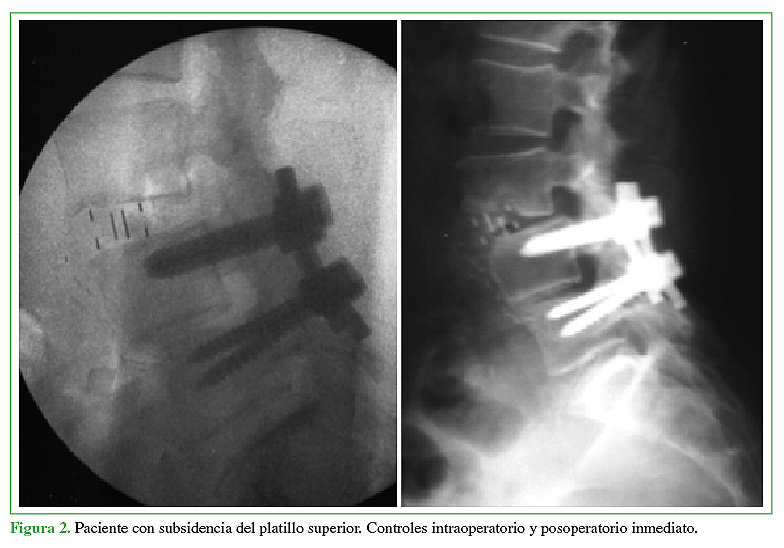

12. Le TV, Baaj AA, Dakwar E, Burkett CJ, Murray G, Smith DA, et al. Subsidence of polyetheretherketone intervertebral cages in mini- mally invasive lateral retroperitoneal transpsoas lumbar interbody fusion. Spine 2012;37:1268–73.

13. Marchi L, Abdala N, Oliveira L, Amaral R, Coutinho E, Pimenta L. Radiographic and clinical evaluation of cage subsidence after stand- alone lateral interbody fusion. J Neurosurg Spine. 2013;19:110–8.